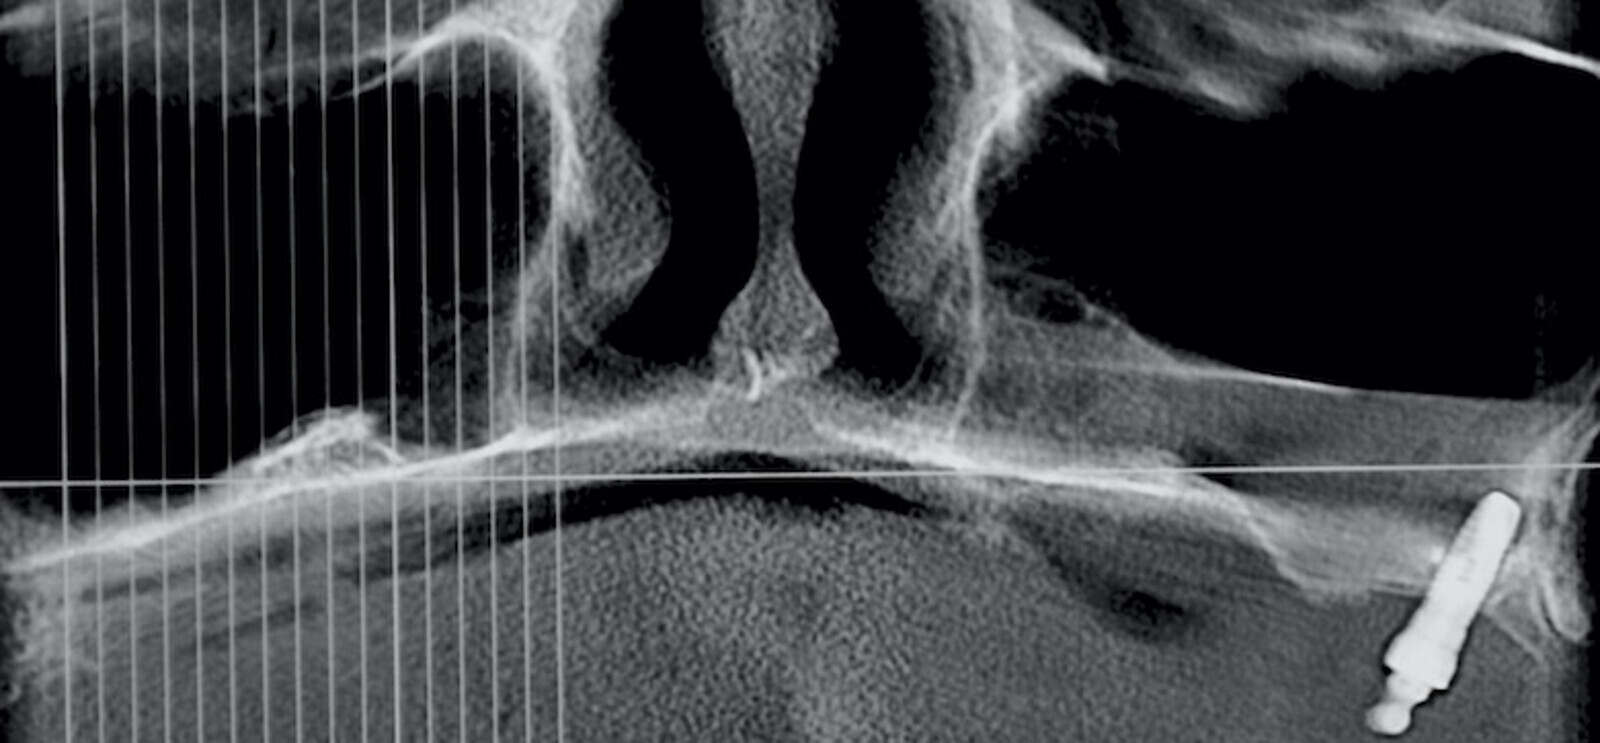

Mario Venturini, director del Instituto de Cirugía Maxilofacial en Rosario, Argentina, nos cuenta el tema que impartirá en la Jornada Virtual de Implantología de AIOI, que versará sobre “Implantología con anclaje extramaxilar”, técnica que permite reconstituir el arco dentario completo del paciente.

La implantología impulsó una mejora en la calidad de vida de los pacientes, mejorando notablemente no solo su confort y estética sino también su autoestima. Aunque pareciera poco y no lo es, evitó dañar más piezas dentarias para lograr un mismo resultado. Si todo ello es cierto, válido y genuino, el anclaje extramaxilar vino más aún, hace ya tiempo, a dar otro gran salto en la resolución quirúrgico protésica en un sesgo de pacientes que seguían excluidos de los beneficios de la implantología por razones obvias: carecían de stock óseo donde implantar.

La implantología volvió a los pacientes más ambiciosos y demandantes de importantes rehabilitaciones, y con justa razón. Hoy en día, prácticamente no hay límites ni etarios ni resortivos-resectivos en los cuales no pueda lograrse la mayor de las rehabilitaciones, el mayor gold estándar, al que los pacientes pueden aspirar: me refiero, ni más ni menos, que a reconstituir su arco dentario completo fijo. Incluso con la posibilidad de remoción y mantenimiento que un simple mortal no implantado no tiene.